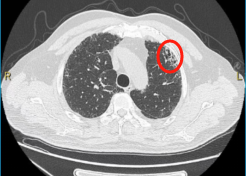

▲2019年胸部CT显示,少许间质性肺炎

(画圈处)改变